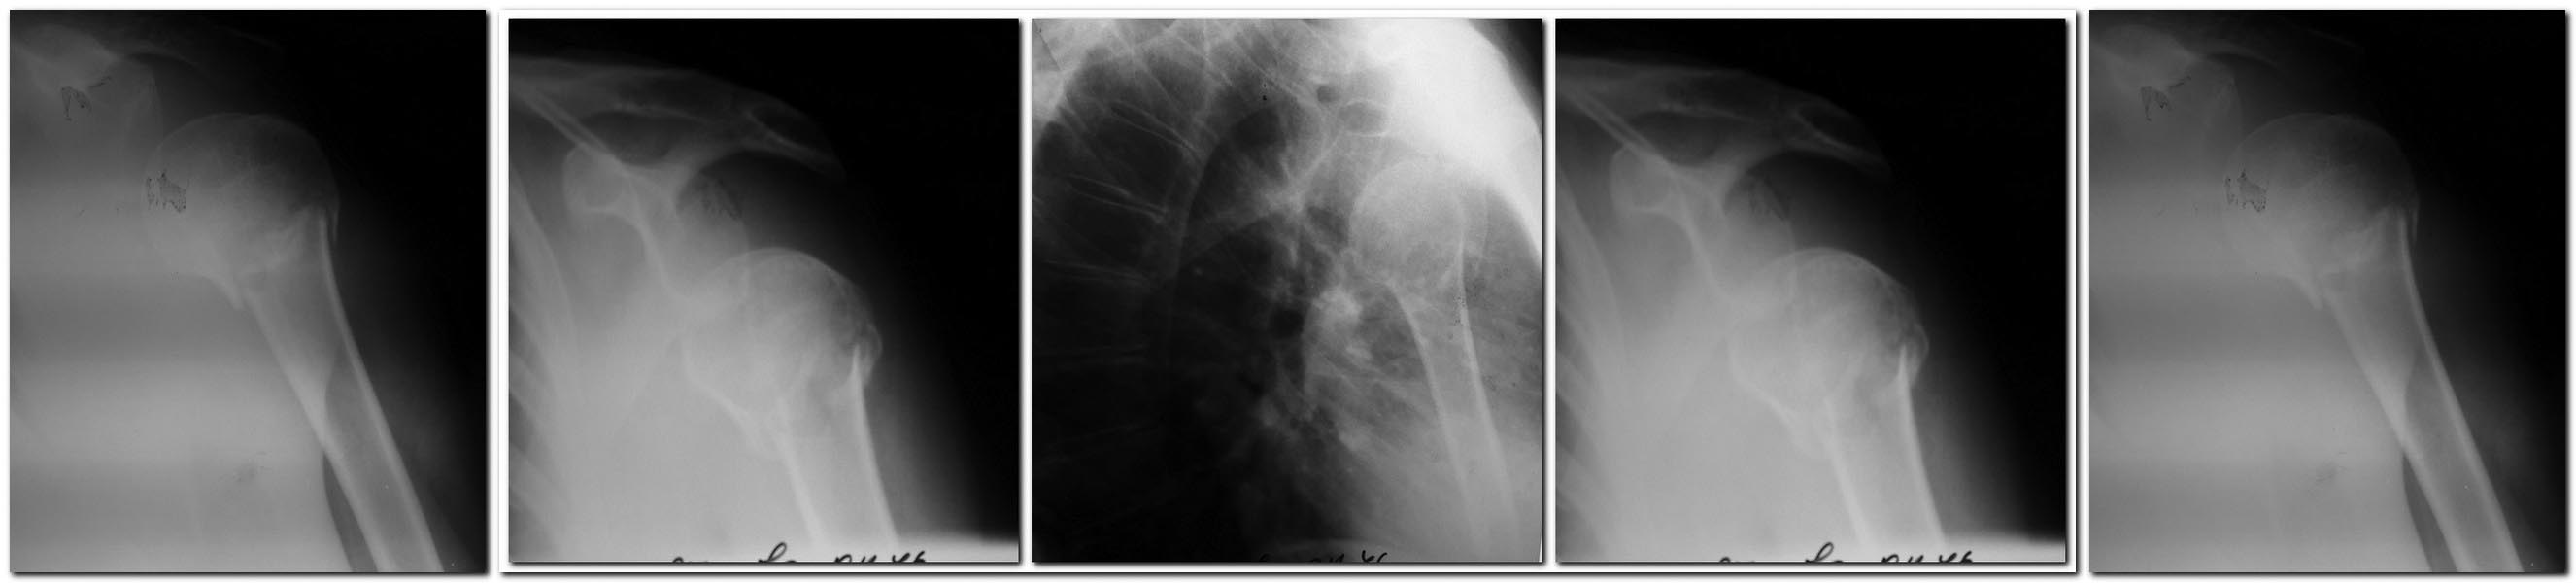

Уважаемые коллеги!

Планирую ревизию надостной мышцы, при ее разрыве -шов. Синтез

проксимальным гвоздем (доступна и пластина LCP). Время с момента

травмы-2 недели. Правильна ли тактика? Какие подводные камни могут

встретиться? Допустима ли трансартикулярная фиксация спицами в случае

неустранимого подвывиха? Спасибо.